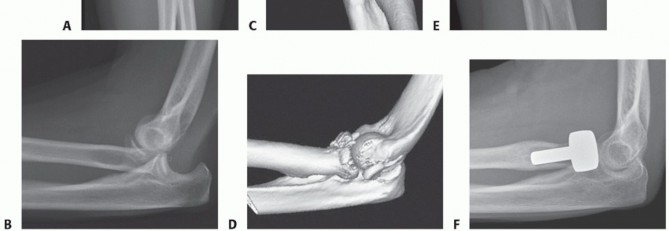

Patients who are known to have, or are likely to have, an associated ligamentous injury of the elbow or forearm should have a radial head arthroplasty because radial head excision is contraindicated (FIG 2).29

FIG 2 • A,B. AP and lateral radiographs of a 54-year-old woman who sustained a posterolateral elbow dislocation associated with a comminuted fracture of the radial head and coronoid—the “terrible triad.” C,D. Preoperative 3-D reconstruction images demonstrating a comminuted radial head fracture with a small undisplaced coronoid fracture. E,F. Postoperative radiographs after modular radial head arthroplasty (Evolve, Wright Medical Technology, Arlington, TN) and repair of the lateral collateral ligament. Medial collateral ligament and coronoid repairs were not required because the elbow was sufficiently stable at the end of the procedure. A good functional outcome was achieved at the final follow-up.*